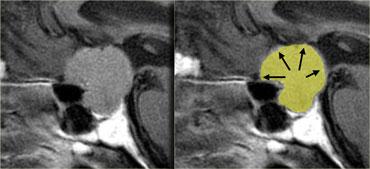

Trên các hình ảnh trên, có thể thấy tuyến yên bình thường, giao thoa thị giác bình thường và động mạch cảnh bình thường ở mỗi bên.

Tuy nhiên, cuống tuyến yên không thể xác định được do có một khối tròn ở vùng này.

Khối này có tín hiệu cao trên chuỗi xung T1W không tiêm thuốc tương phản từ.

Chỉ có hai thành phần cho tín hiệu sáng như vậy trên chuỗi xung T1W không tiêm thuốc tương phản từ, đó là: dịch (máu hoặc dịch giàu protein) hoặc mỡ.

Các khối đặc không có tín hiệu sáng như vậy.

Do đó, nhiều khả năng đây là một cấu trúc dạng nang có nguồn gốc từ cuống tuyến yên, có thể là nang khe Rathke.

Sọ hầu bào dạng nang cũng nằm trong chẩn đoán phân biệt.

Các hình ảnh này minh họa tầm quan trọng của chuỗi xung T1W không tiêm thuốc tương phản từ.

Chúng cho phép xác định rằng bất thường chỉ khu trú tại cuống tuyến yên.

Nếu chỉ xem các hình ảnh sau khi tiêm thuốc tương phản từ tĩnh mạch, có thể nhầm lẫn rằng bản thân tuyến yên cũng bất thường.